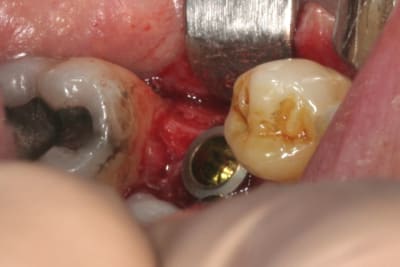

place aux photos!!!

forage, tout ce qu'il y a de plus classique pour ceux qui connaissent ID ou zimmer

pour un implant de 5mm de diamètre on s'arrête au foret de 4.4, passé ici sur 8mm au lieu des 11.5mm car j'étais dans du D3